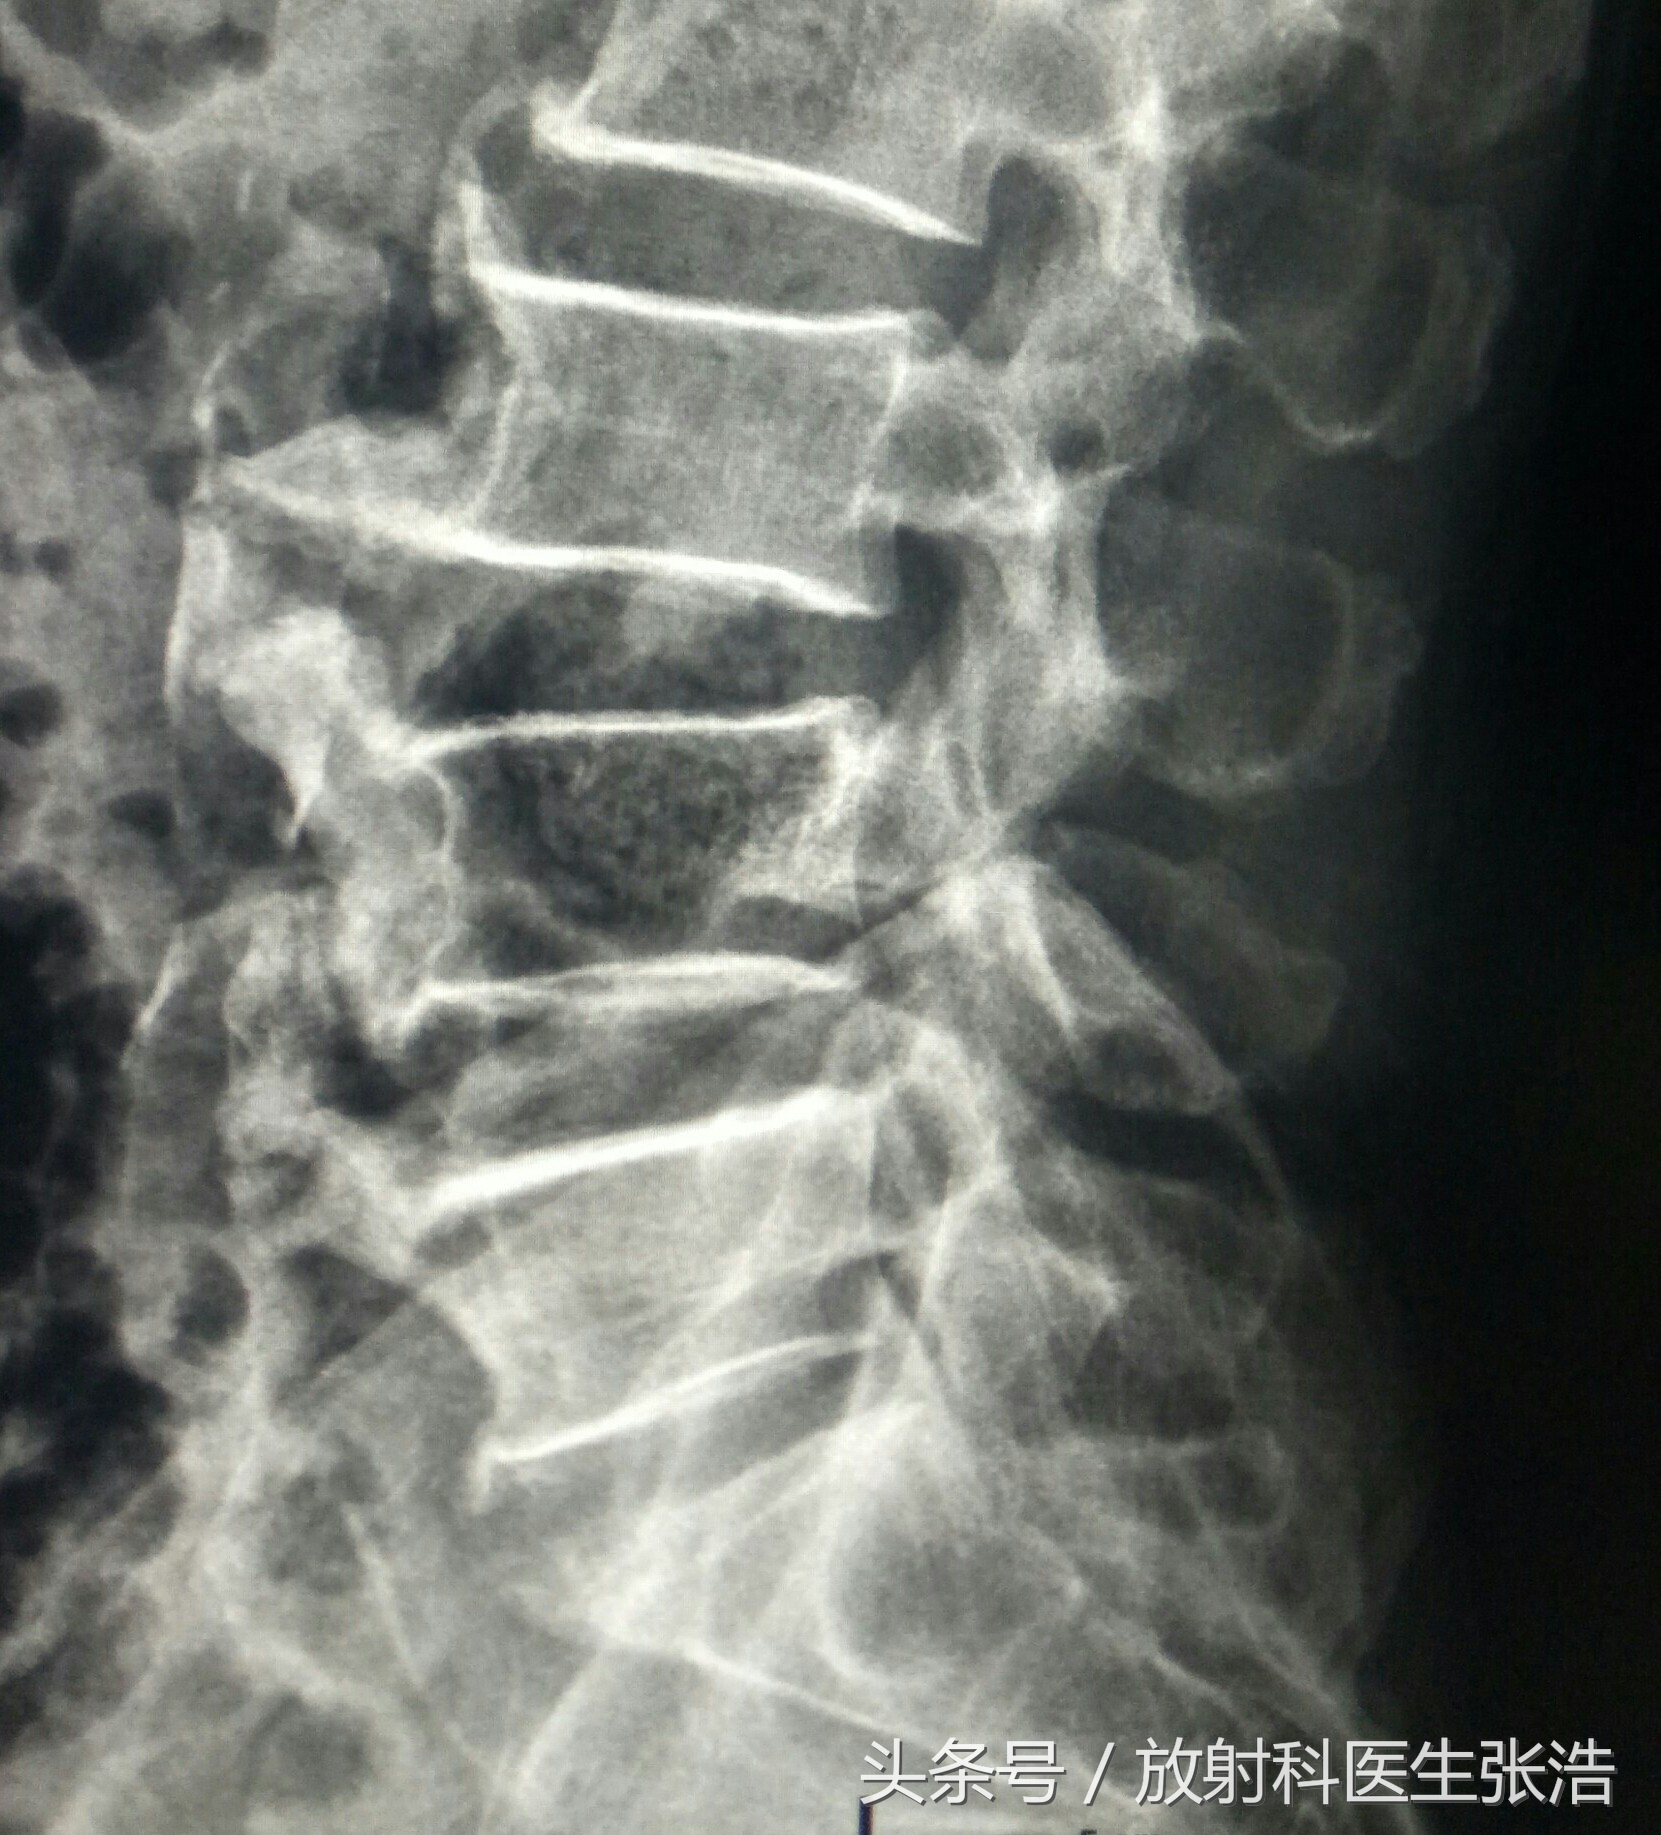

上面这是腰椎和颈椎增生的患者,可以看到椎体缘有明显的骨质增生,因为椎体前后有前纵韧带后后纵韧带,过多的增生往往会影响其活动度,有的增生会压迫到硬膜囊神经根等,所以会导致要背脖子僵硬不适。